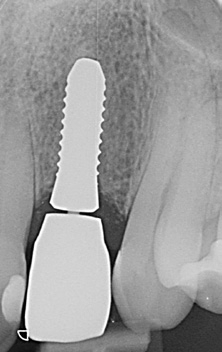

Nach einer Ästhetikeinprobe wurde die Zirkoniumdioxidkrone mit Multilink Hybrid Abutment Zement (Ivoclar Vivadent) auf dem PEKK-Abutment verklebt (Abb. 25–28). Die Klebeüberschüsse wurden entfernt, die subgingivalen Anteile sorgfältig poliert und gereinigt. Die Abbildung 29 zeigt das individuell ausgeformte Weichgewebsprofil vor der definitiven Insertion der Hybridabutmentkrone, die mithilfe einer neuen Titanabutmentschraube eingesetzt wurde. Nach dem Einsetzen der Versorgung mit 25 Ncm wurde eine Röntgenkontrollaufnahme angefertigt. Da das Hochleistungspolymer nicht röntgenopak ist, bedarf es etwas Erfahrung bei der Passungskontrolle. Die Aufnahme sollte im rechten Winkel zur Plattform auftreffen, um dann eine parallel verlaufende dunkle Scheibe in einer Höhe von 0,55 mm über dem Implantat zu erkennen (Abb. 30 und 31). Mithilfe von Zusätzen, wie z. B. Bariumsulfat, könnte der Hochleistungskunststoff röntgenopak gefertigt werden. Allerdings würden diese das Material schwächen, wodurch die herausragenden Eigenschaften von PEKK, wie Stabilität, Duktilität und Abdichtung, minimiert würden. Beim Followup nach zwölf Monaten zeigten sich eine stabile Weichgewebesituation und geschlossene Interdentalräume (Abb. 32).